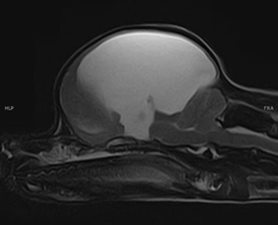

- Imagerie par résonnance magnétique (IRM)